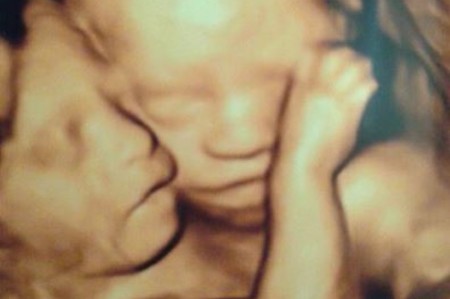

A Hastings, Minnesota, woman who gave birth to conjoined twin girls last week but is now grieving the loss of one which died during an operation to separate the sisters, is also giving thanks to God through her heartbreak. Amber McCullough, a 31-year-old U.S. Army Reserves captain and attorney, gave birth to Hannah and Olivia via Cesarean section at just 32 weeks into her pregnancy at Children's Hospital Colorado.

When doctors initially told McCullough that her girls were conjoined twins — a rare condition that occurs just once every 200,000 births, according to the University of Maryland Medical Center — they said there was a high chance they could be stillborn. Although the girls shared an abdomen, liver and intestinal tract, Olivia had an especially low chance of survival because her heart had only one ventricle, and she had only one leg and a congenital brain malformation.